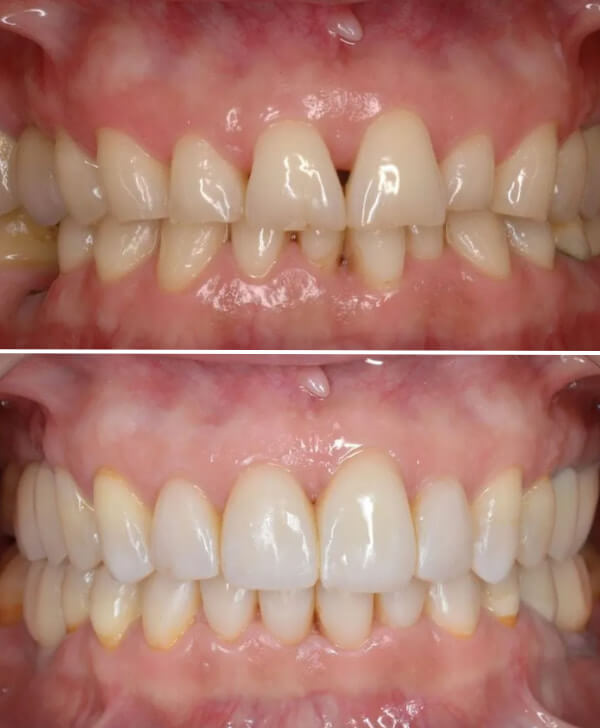

Resultados del tratamiento

Antes y después de tratar el bruxismo y las troneras dientes

• Desaparición del dolor y de las molestias continuas.

• Corrección del bruxismo como causa principal del problema.

• Reconstrucción dental estable y funcional.

• Recuperación de la sensación de bienestar y normalidad en la boca.

Este tipo de casos demuestra que las troneras dentales, en algunos pacientes, pueden ser la consecuencia de otros trastornos bucodentales, por lo que realizar un diagnóstico completo resulta clave para aplicar el tratamiento adecuado.